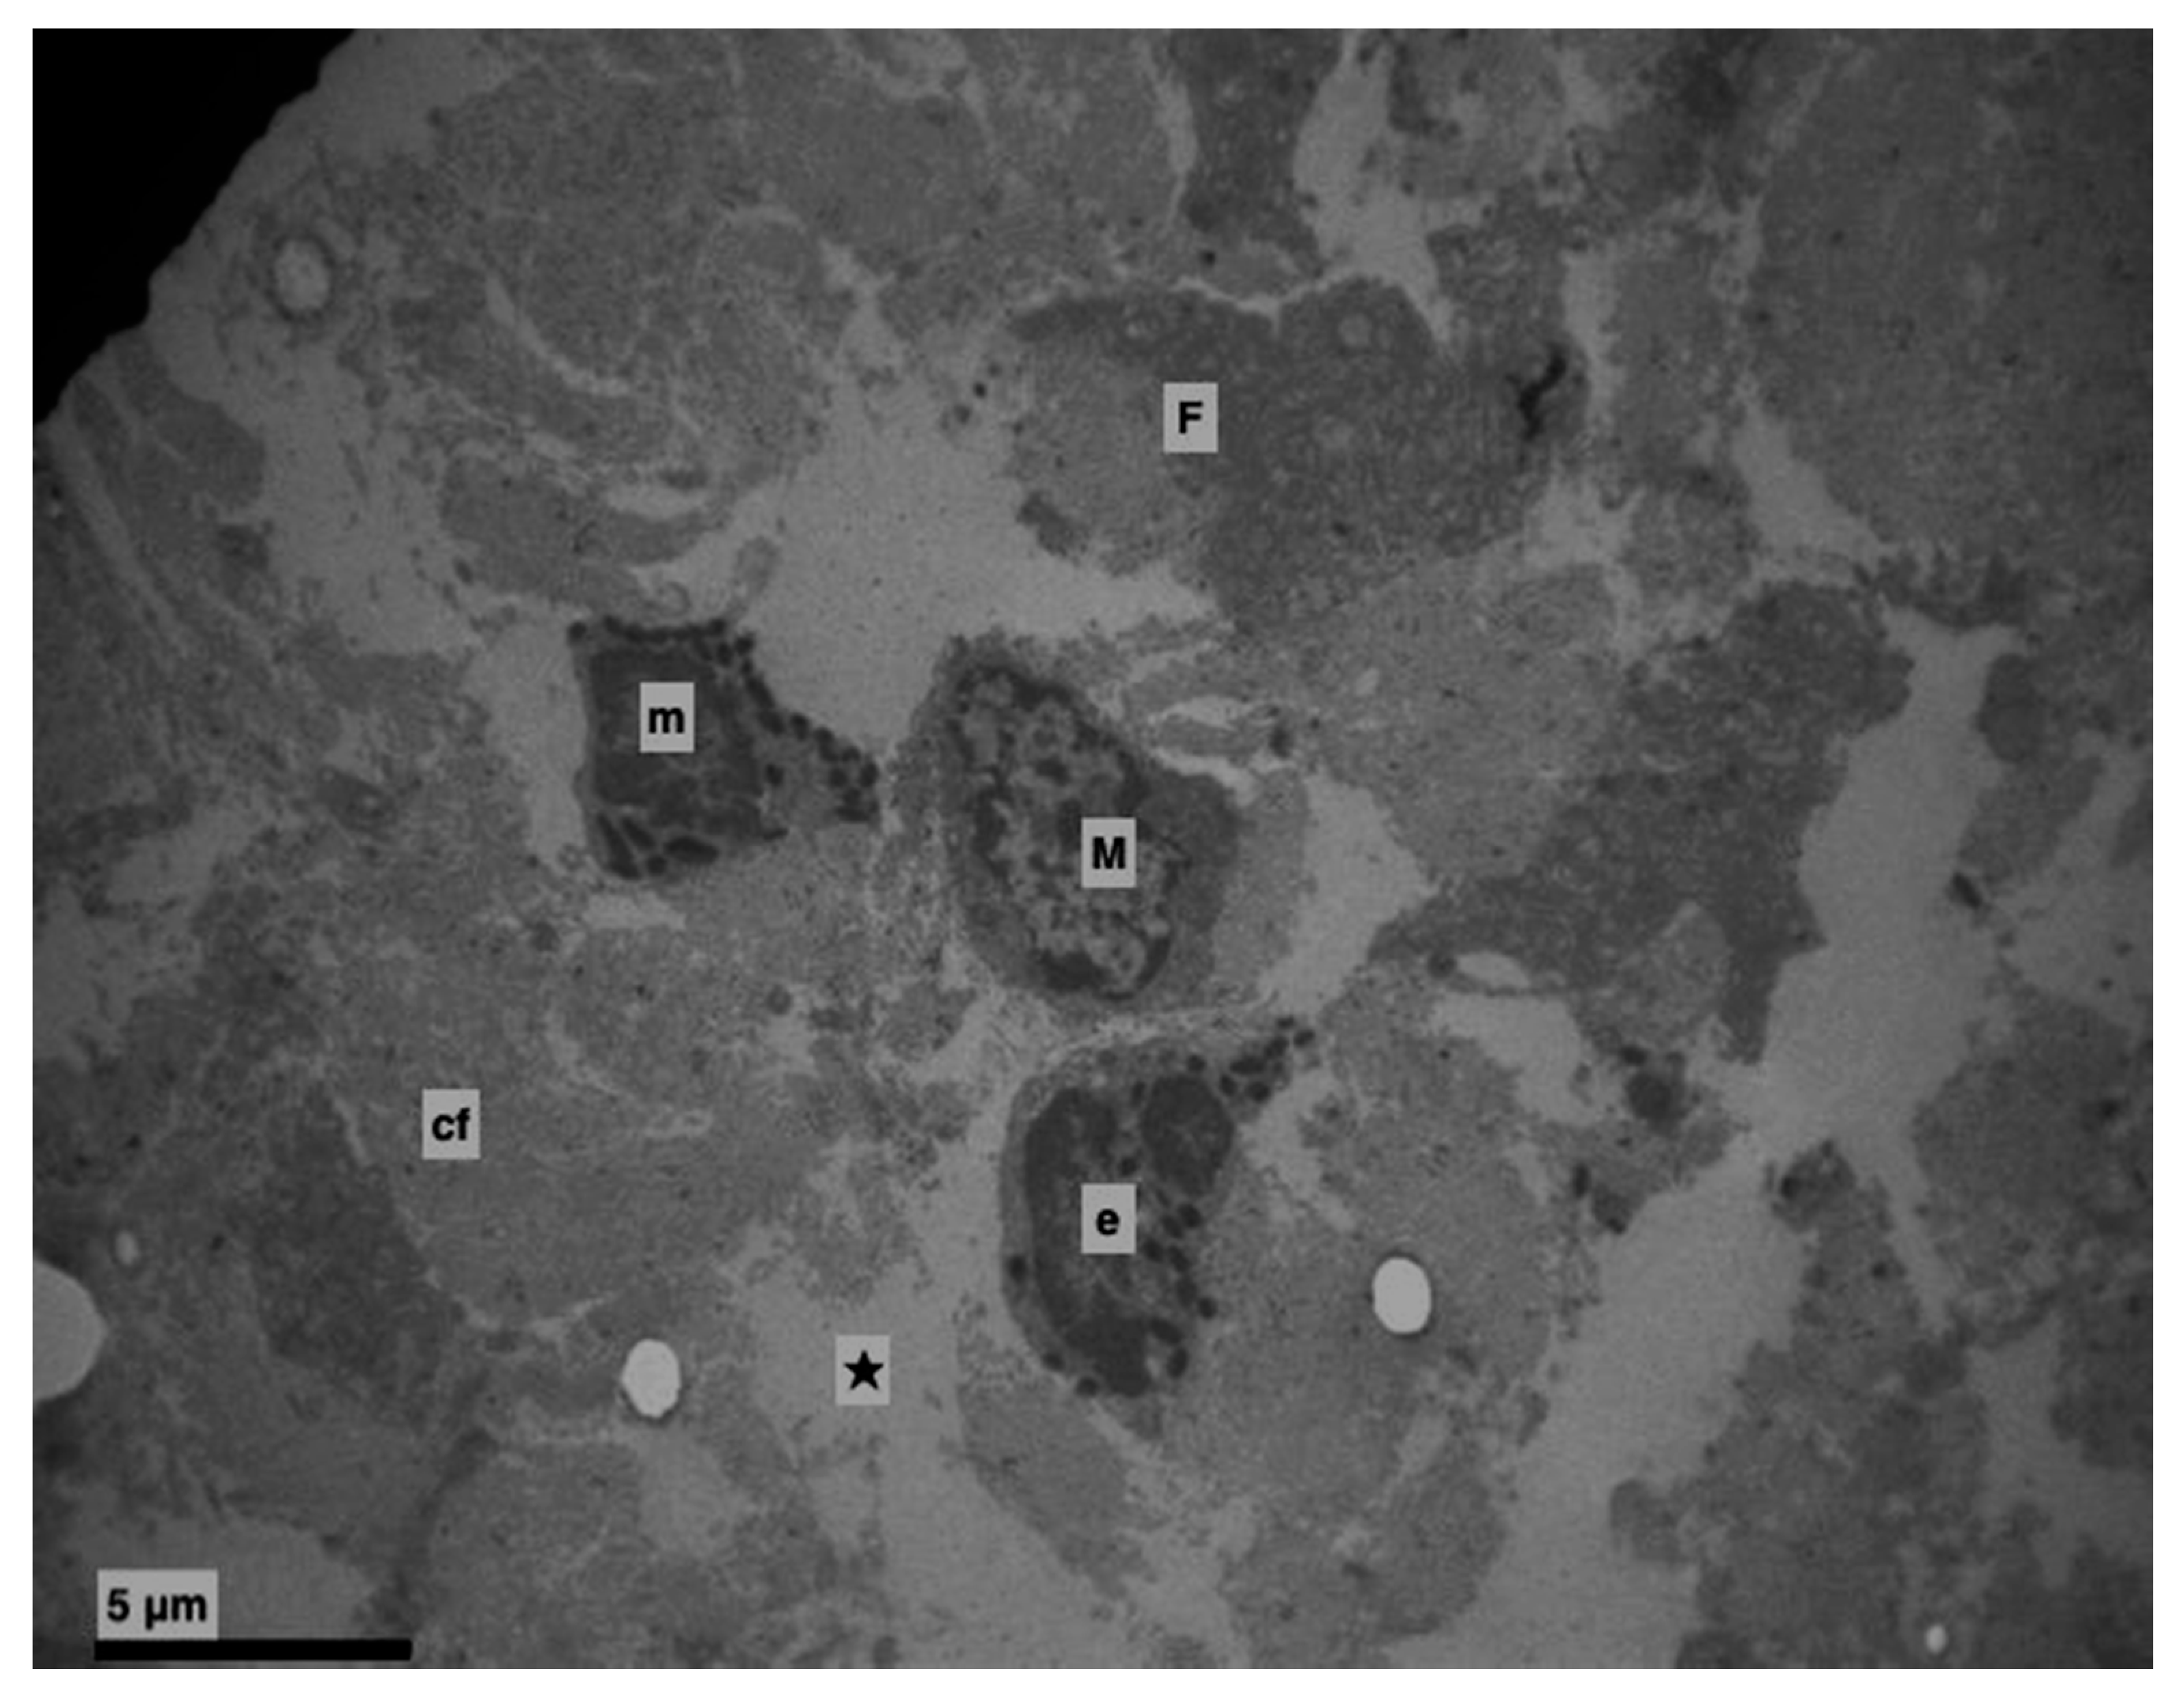

3. Results